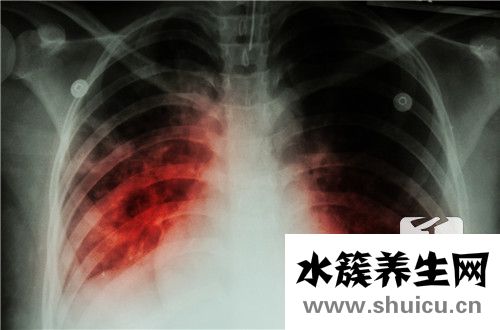

毫無疑問,在發(fā)生肺氣腫后,患者人體的各個(gè)方面都會(huì)受到很大影響。 主要原因是肺是人體核心吸入呼吸系統(tǒng)中的人體器官。 呼吸將受到很大影響。 在治療肺氣腫的整個(gè)過程中,除了開處方控制病情發(fā)展的藥...